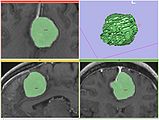

FastMarching segmentation module in Slicer 3.6: Segmentation of a meningioma